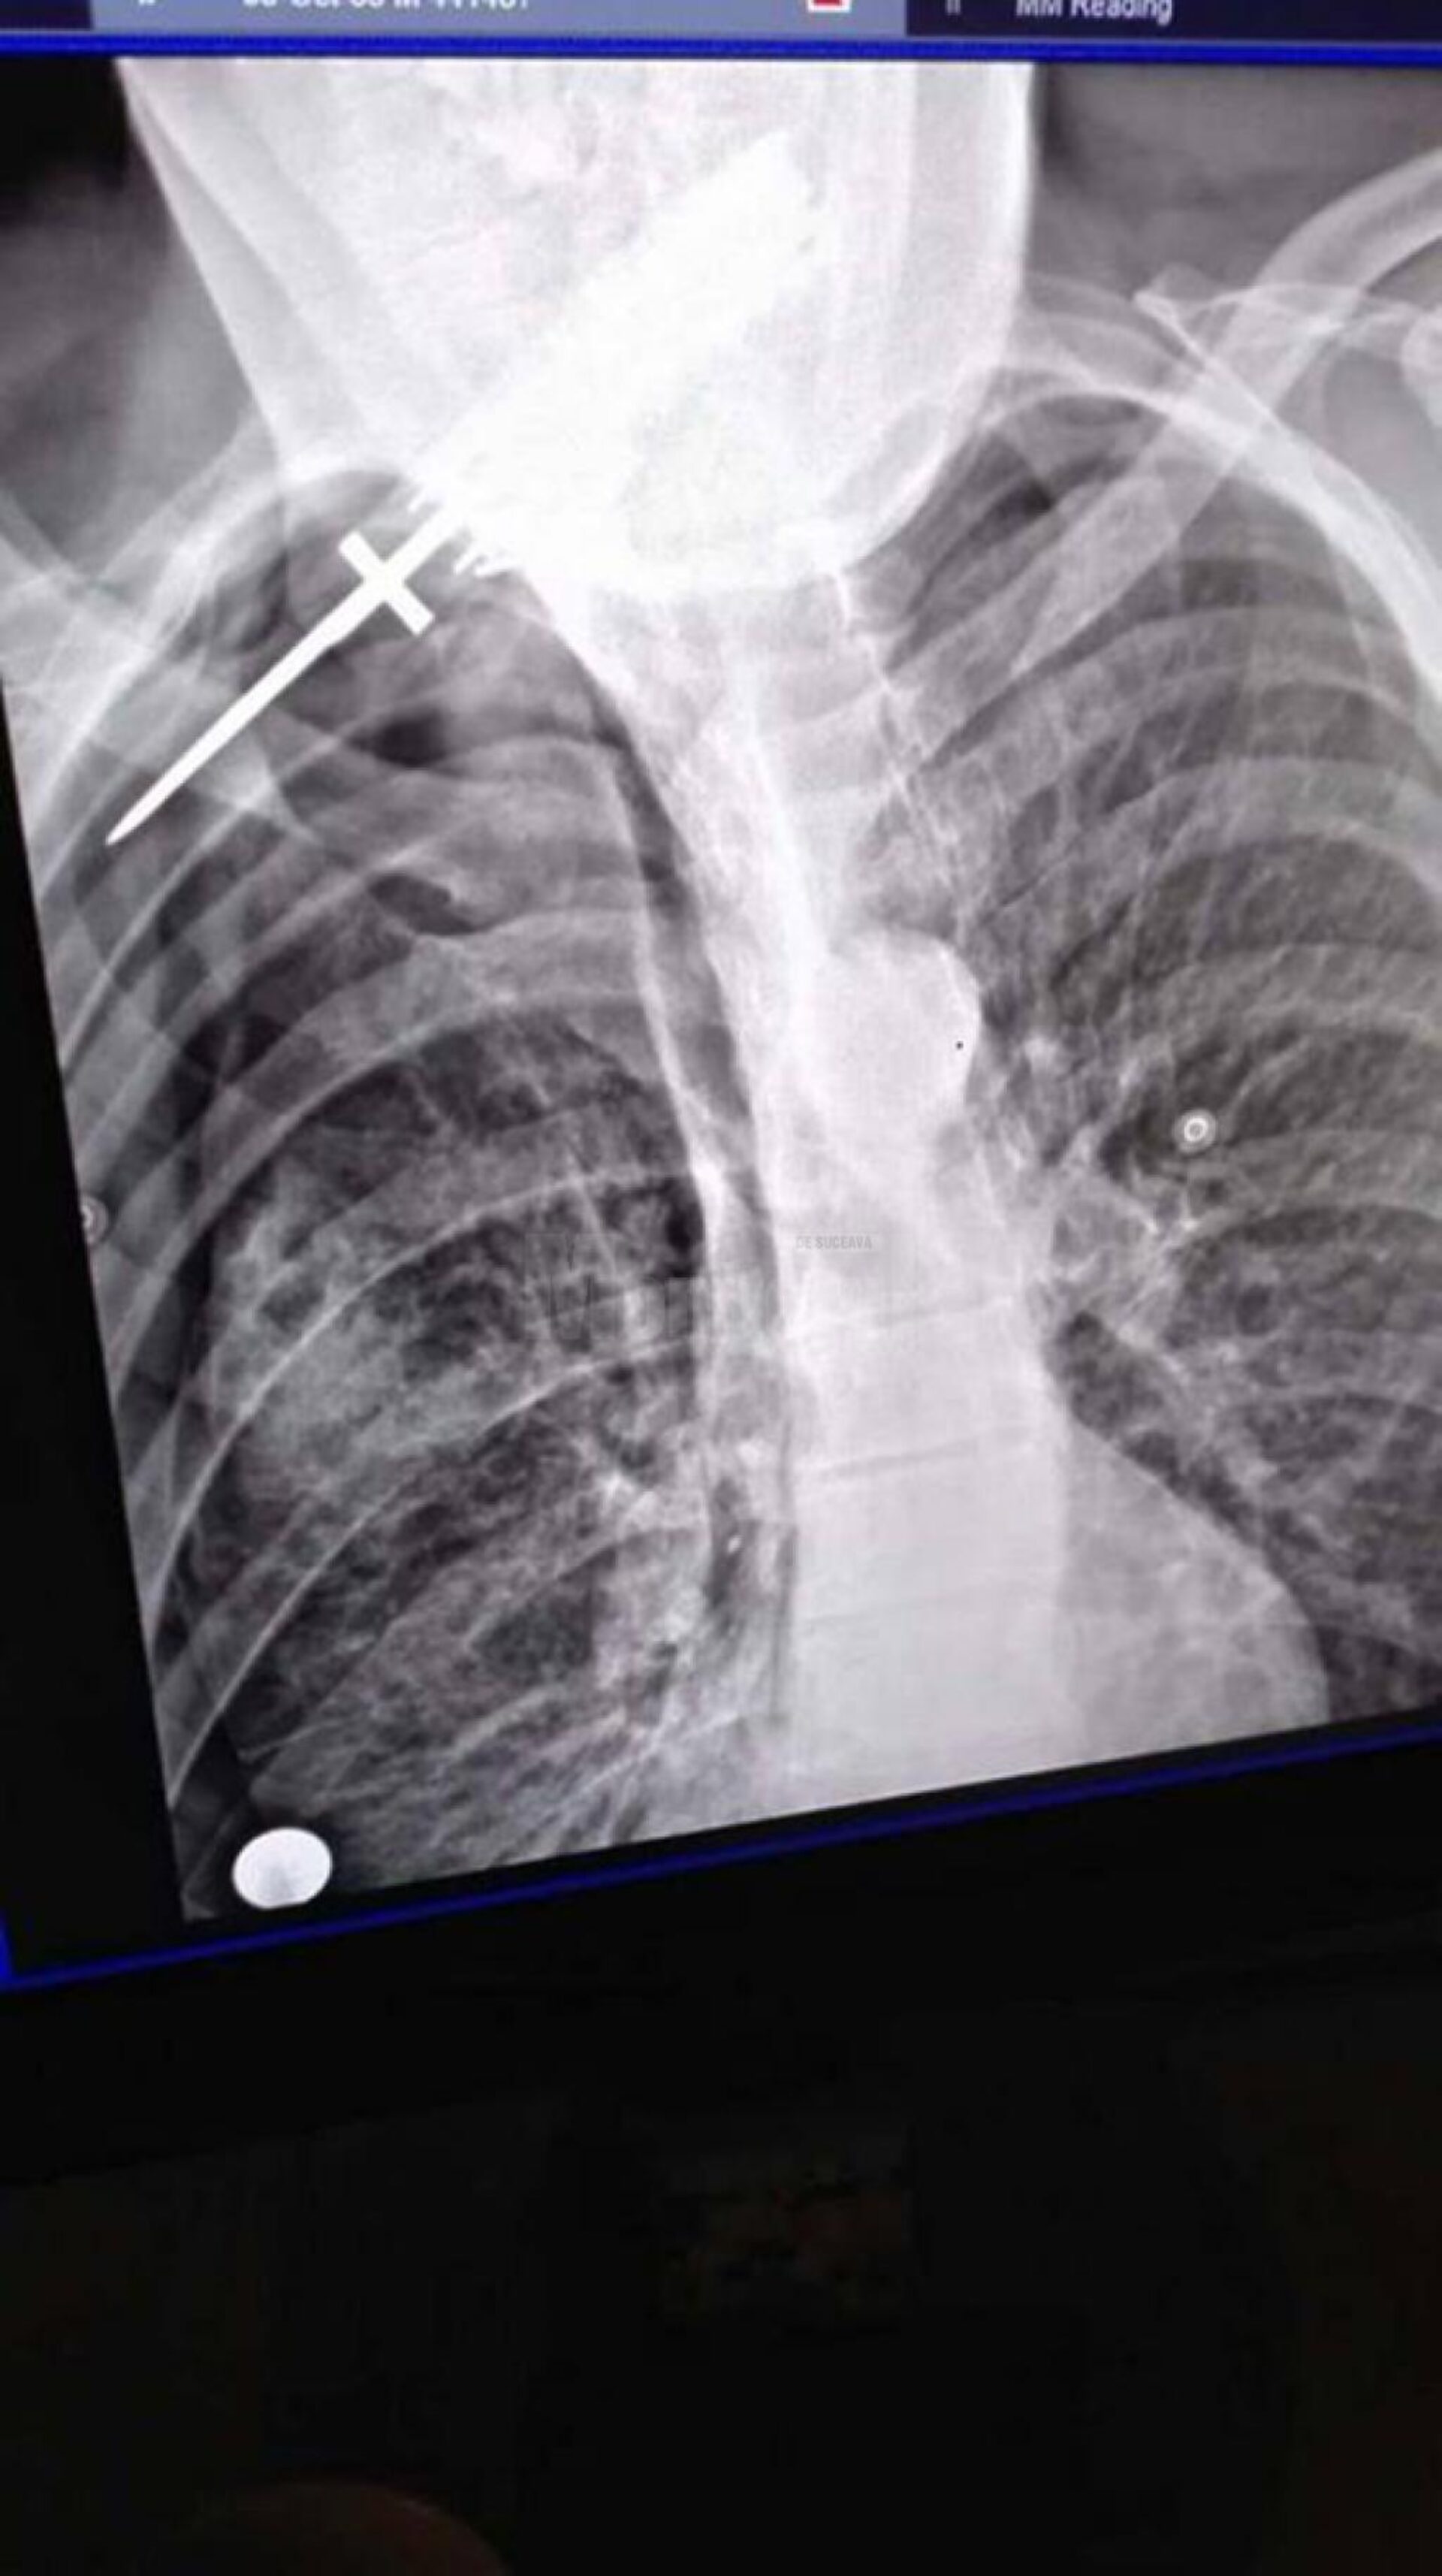

Pe 11 iunie, în jurul orei 23.45, Postul de Poliție Arbore a fost sesizat prin 112 de Luminița Covaci, din satul Clit, comuna Arbore, care a anunțat că Neculai F., de 53 de ani, concubinul ei, a fost înjunghiat. Bărbatul a fost transportat la Spitalul Județean Suceava, unde a fost diagnosticat cu plagă înjunghiată hemitorace dorsală, cu retenție de corp străin – cuțit. Practic, bărbatul a ajuns la spital cu cuțitul în spate. El a fost operat de urgență, pentru pneumotorax traumatic și pentru extragerea corpului străin.

Bărbatul înjunghiat a fost diagnosticat cu leziuni care necesită 22-23 zile de îngrijiri medicale, medicul legist apreciind că nu i-a fost pusă viața în primejdie. Având în vedere modul în care a acționat femeia, lovitură de cuțit în zona organelor vitale, fapta a fost încadrată totuși la tentativă de omor.